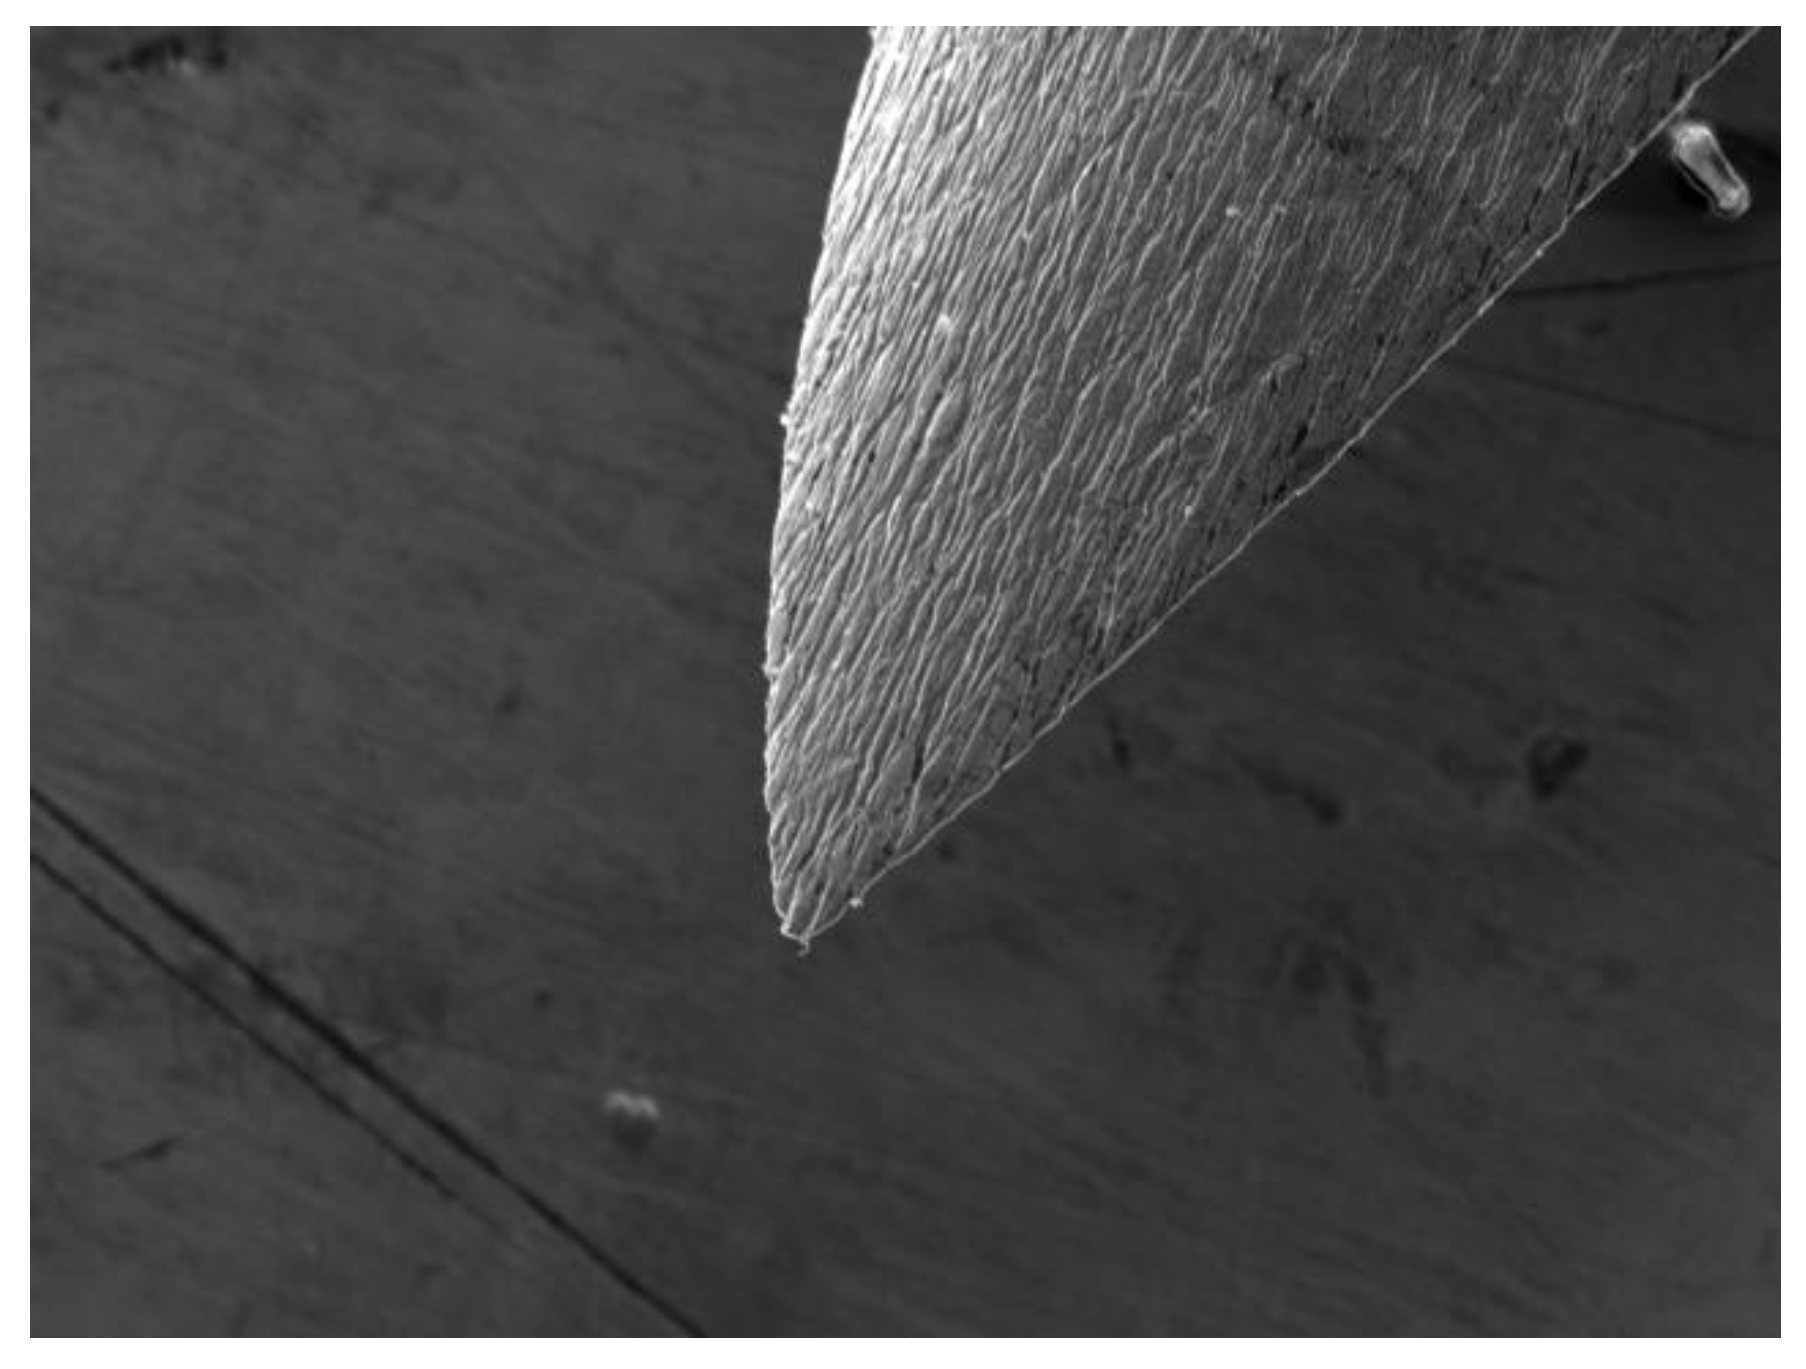

In order to reduce both the painful sensation of the needle pricking the tissues and the trauma induced on them, the end of the needle has a particular bevel shape which, sharp and cutting, easily penetrates both the mucosa and the soft tissues below (Figure 1).

Figure 1. Needle bevel, SEM observation, convex side.

Preprints 111024 g001